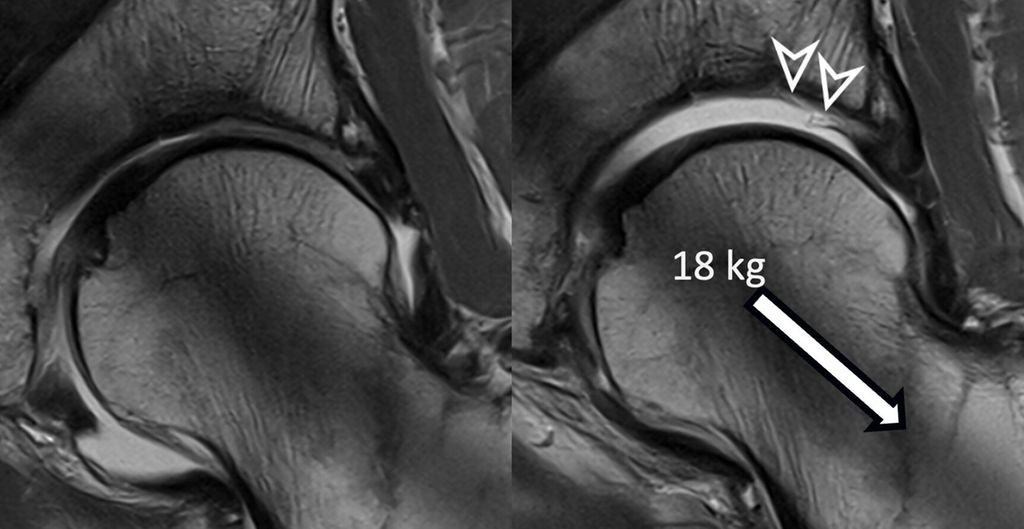

Traction MRI of the hip for improved detection of macroscopic cartilage damage

The hip is a ball-and-socket joint with the labrum dividing it into peripheral and central compartments. In standard MR arthrography, a contrast agent expands the hip capsule and flows into the central joint cavity through the acetabular notch. However, most of the contrast does not spread centrally due to the opposing femoral and acetabular cartilage layers, which typically prevent its accumulation unless there is significant cartilage damage. Therefore, visualizing acetabular cartilage delamination which represents a typical and frequent finding in patients with cam-type FAI is challenging with direct MR arthrography.4

To improve visualization of the central joint cavity during MR arthrography, axial leg traction can be applied, similar to the joint distraction needed during hip arthroscopy (Fig. 1). Traction MR arthrography of the hip has shown high accuracy in detecting chondrolabral lesions, ligamentum teres injuries, and intra-articular loose bodies and has demonstrated its value in predicting failure of FAI surgery.5–8 It is particularly helpful for better visualizing the extent of cartilage damage in older patients with mild radiographic joint degeneration and thus aid in surgical decision making. Traction MR arthrography can also detect unstable labral tears in patients with hip dysplasia and may aid in planning treatment for femoral head necrosis in young patients with early collapse and preserved joint space.4